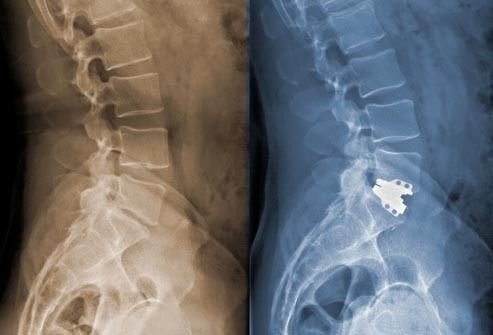

אתה נותן לי גב?

כאבים ברגליים הנגרמים בעקבות בעיית גב התחתון